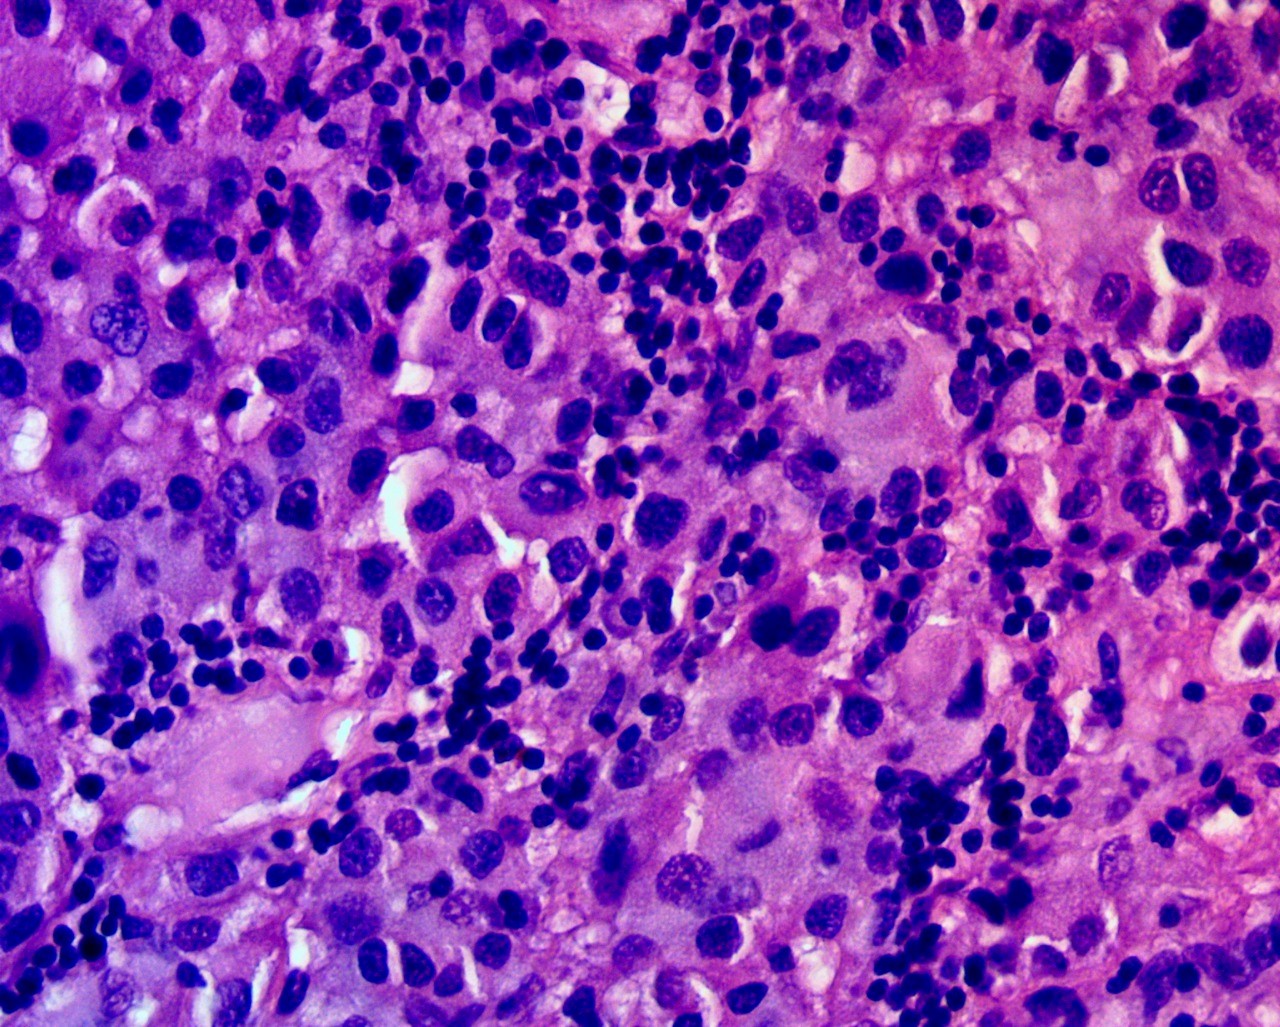

Макроскопическое описание удаленного операционного биоматериала образования ГМ: фрагменты ткани белого цвета, дряблой консистенции, размерами по 25 × 10 мм. Микроскопическое описание: фрагменты ткани ГМ с инвазивным ростом образования, построенного из атипичных полиморфных клеток с эозинофильной цитоплазмой, четкой клеточной стенкой, формирующей солидные поля. Отмечаются участки некрозов, очаговая нейтрофильная и лимфоплазмоцитарная инфильтрации (рис. 4). Материал направлен на ИГХ.

Рис. 4. Гистологический препарат метастаза меланомы с воспалительной инфильтрацией. Окраска гематоксилином и эозином, ×400

Fig. 4. Histological preparation of melanoma metastasis with inflammatory infiltration. Staining with hematoxylin and eosin, ×400

При проведении ИГХ отмечается диффузная цитоплазматическая экспрессия S100, Ki67 — до 15%, очаговая экспрессия HMB45, ядерная экспрессия p53 в единичных клетках, отсутствует экспрессия CK7, CK20, GFAP, PanCK в клетках опухоли (рис. 5).

Патоморфологическое заключение: гистоморфологическая картина метастаза беспигментной эпителиоидной меланомы в ГМ.